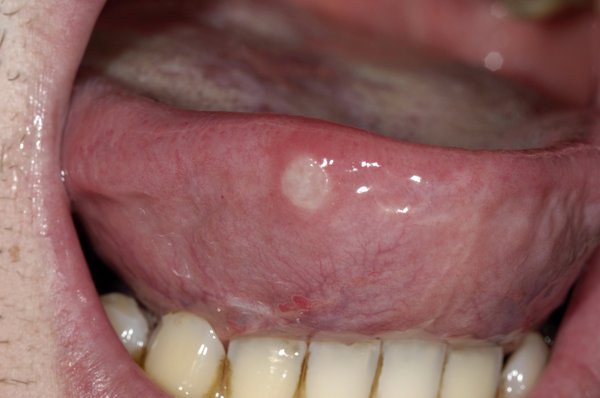

혓바늘, 흔히 혀에 생기는 작은 상처나 염증을 의미한다. 이러한 혓바늘은 매우 드물편이지만 문제는 불편하고 통증이 있다는 점이다. 특히 음식을 먹거나 말을 할 때 심한 통증이 동반되는데 이러한 혓바늘이 생기는 이유와 혓바늘 없애는법에 대한 이야기를 해보려고 한다.

혓바늘이 생기는 원인은 매우 다양 하기 때문에 콕 찝어서 이야기가 하기가 힘들다. 비타민 B군이 부족한 경우 혓바늘이 생길수 있다는 연구결과가 있다. 특히 비타민 B12와 엽산이 부족한 경우 문제가 되는데 해당 성분들은 세포 재생에 중요한 역할을 하기 때문에 결핍 문제가 발생할 경우 입안에 점막 재생 능력이 떨어지게 되어 혓바늘이 생기기 쉬워진다.

혓바늘 생기는 이유중 피로해서 생긴다는 말을 종종 들어 봤을 것이다. 실제로 피로로 인한 면역력 저하는 단순포진 바이러스에 취약해질수 있다. 면역력이 떨어진 상태에서 더욱 빈번하게 나타날수 있기 때문에 만성피로 또는 독감이나 감기에 걸렸을때도 혓바늘이 생길수 있다.

피로와 유사하게 스트레스 문제도 있다. 스트레스는 신체 면역 기능을 저하시켜 혓바늘 발생 확률을 높이는 요인이 되기 때문에 스트레스와 면역력의 연관성도 무시할수 없고 입안 위생 관리 미흡으로 생기는 세균 증식 또한 혓바늘의 원인이 될수가 있으며 반대로 혓바늘이 생겼다고 양치질 같은 것을 하지 않으면 혓바늘 자연 치유 속도를 늦출수가 있다.

이외에 혓바늘 생기는 이유는 알레르기 문제나 또는 뜨거운 아니면 매운 음식을 먹으면서도 발생할수 있고 산성도가 높은 과일이라 음료를 마시는 경우에도 혓바늘이 발생할수 있다는 점을 유의해야 한다.